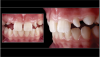

Fig 13. COCO Lux is used here for emergency treatment, blunt force trauma to the right lateral incisor.

Figure 13

Fig 14. Specialist referrals can also be aided by clear photographs. In this case, an image captured using COCO Lux shows the exposure of implant threads and ulcerations under the prosthesis at 2 years.

Figure 14